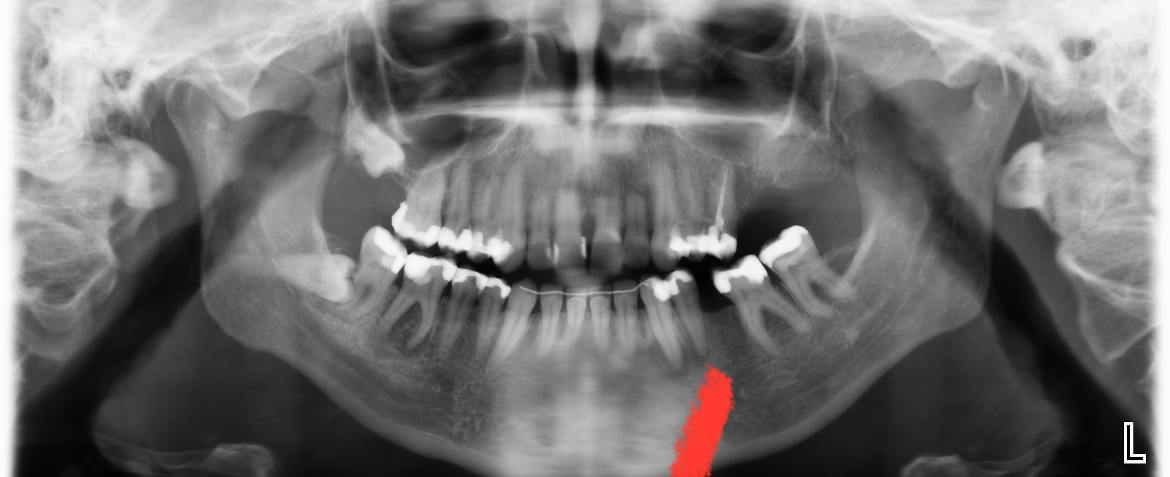

U ziet wat er gebeurt als een kies getrokken wordt en niet wordt vervangen ( zie hoe links onder, 37, uitgegroeid is).

Er zijn ontstekingen aan de 46/ 33/ 34/ mogelijk 25 en gaatjes in de 15/ 14???/24??/25??/45?? moeilijk te zien op deze foto daar zou extra kleine foto's voor gemaakt moeten worden... Zwaar gevulde kiezen waar geen kronen op zijn gemaakt. Problemen met uw bot niveau ( voortanden boven). Roker??. Als u geen financiele middelen heeft zou ik in dit geval een frame prothese overwegen.

Voor een frame prothese zijn de 43/44...33/34....23/24...en 13/14 belangrijk. Dat zijn , ter vergelijking, de haakjes v e kapstok om een jas (frame) aan op te hangen. Helaas zijn sommigen zwaar gevuld en indien mogelijk zou ik daar een kroon op laten maken.Dat hoeft niet in een keer maar kan gelijdelijk naarmate u dit financieel, op termijn, kunt (wil????velen hebben er niets voor over en geven het geld liever aan andere, luxe [vakantie, kapper?] , zaken uit) uitvoeren.Voor een frame zou ik nu al (ontsteking) de 46 verwijderen. Dat geld kunt u beter aan herstel v d 33/34 besteden. 33 Cruciaal voor een frame...eventueel de 34 laten gaan. Zo lang mogelijk andere kiezen behouden om intussen de cruciale kiezen (al duurt het een p jaar) te bekronen. Wel echt een strak tijdsplan maken anders gebeurt er niets en is het te laat , nu al een voor twaalf. Of de keuze maken om af te bouwen , op termijn (hoeft niet gelijk), naar een kunstgebit. Wel zorgen dat er geen gaten en vooral ontstekingen zijn.

Een tand/kies verwijderen heeft invloed op de gekozen behandel strategie voor de toekomst. Dat heeft u besproken/beslist met uw tandarts, dat is niet aan de KC om met u te bespreken. DE KC geeft aan extractie , uw tandarts wil het terecht proberen als dat in de behandel strategie v behoud en geen uitneembare vervanging past. Dus de keuze v wkb of trekken heeft daar invloed op. U vraagt of uw kiezen kunnen verschuiven...ja.... hoeveel is voor mij niet in te schatten.

Uheeft een x-foto mee gestuurd. Daar heb ik op gereageerd met wat ik zie. Omdat ik de behandel strategie voor de toekomst niet weet heb ik een voorzet gegeven v een v d mogelijkheden (frame) en wat daarvoor nodig is, de zichtbare valkuilen.. Een frame indien de 46 getrokken wordt en geen WKB (duidelijk te zien op de eerste x-foto) gekozen wordt. Met dat advies kunt u doen wat u wilt.

Vanwege het botverlies bij de voortanden vroeg ik mij af of u rookt of gerookt heeft...gelukkig niet.Wat heeft u voor de toekomst bepaald??.